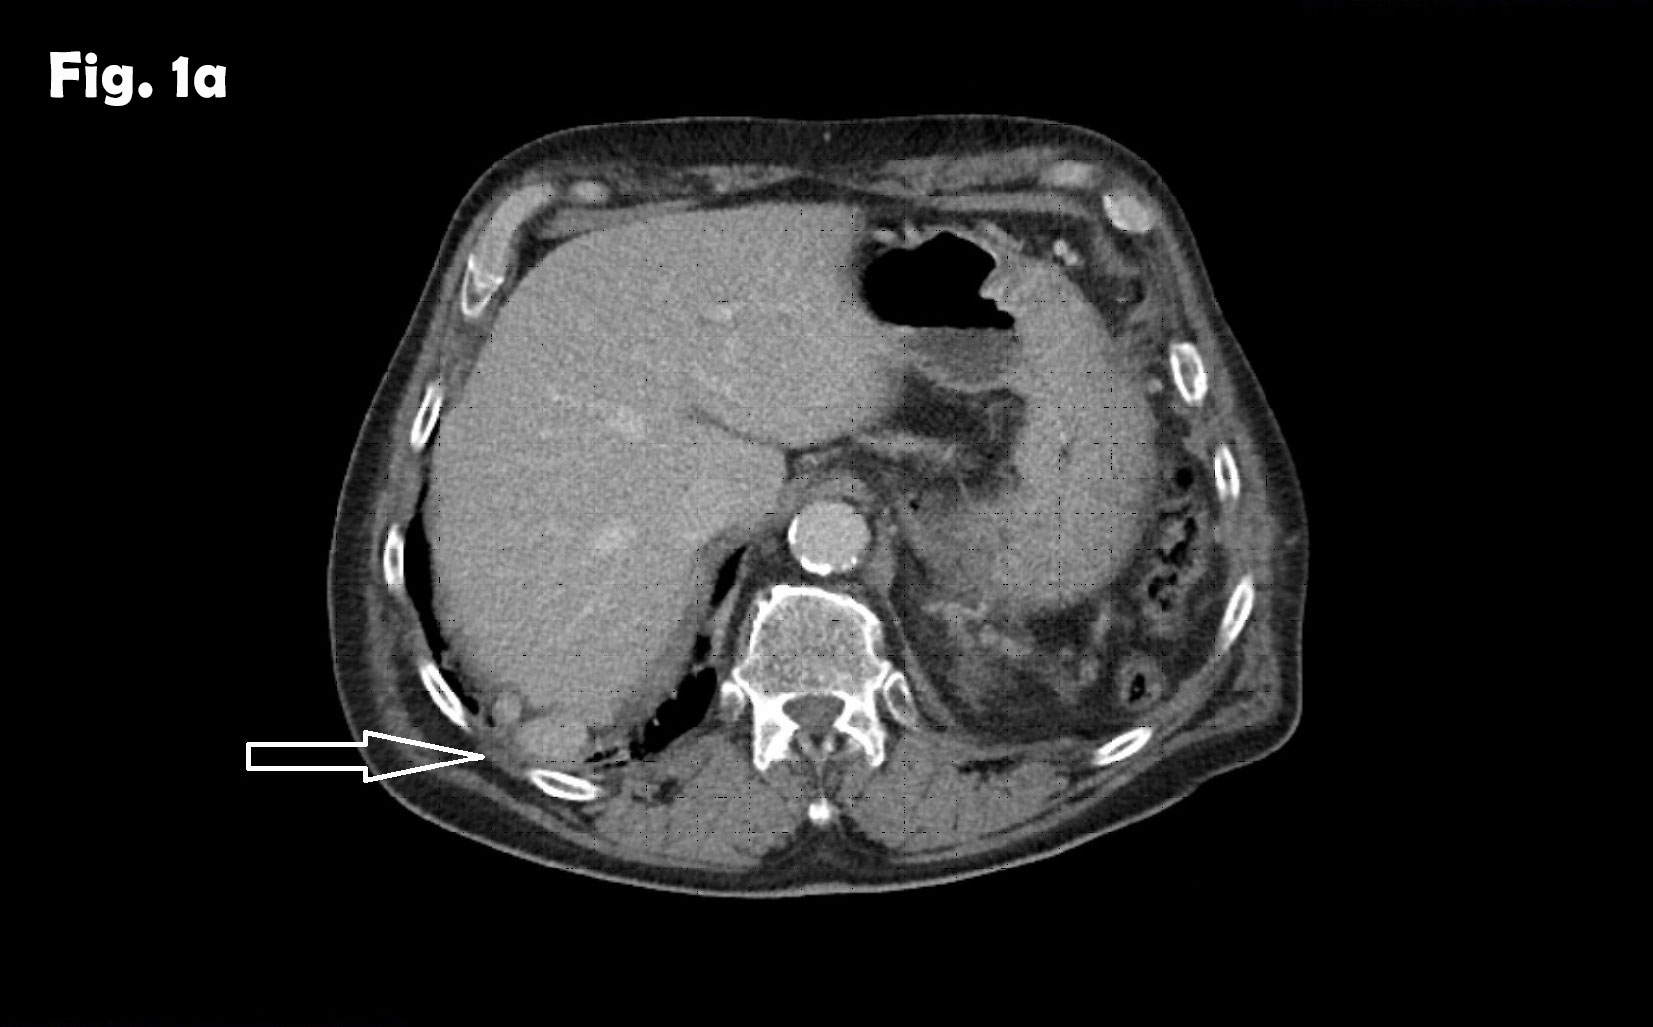

Computed tomography of the abdomen demonstrated no spleen and numerous small nodules of up to 28 mm between intestinal loops and between the liver and diaphragm suggesting a disseminated neoplastic process, thought to be most probably, peritoneal carcinomatosis. The arrow on the scan illustrates the lesion that was biopsied which excluded neoplasia and demonstrated splenic tissue.

Computed tomography of the chest revealed pneumonic infiltration but was otherwise normal. The endoscopic examination of the upper and lower gastrointestinal tract was normal. Contrast enhanced ultrasound (CEUS) showed arterial and late phase enhancement lasting more than 5 minutes in all examined nodules. After Biopsy the ultrasound examination was performed showing multiple almost echofree but also echogenic round and oval shaped focal peritoneal masses with a size of up to 46 mm [Figure 2-4].